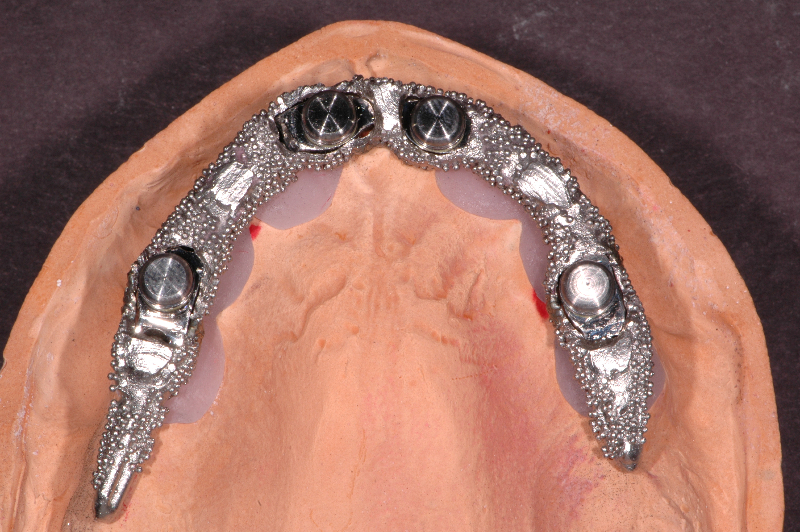

From www.wiandlab.com

CAD/CAM Implant Bar Design in Arizona Titanium Dental Implant Bars Titanium Bar For Dental Implants    learn about the different grades of titanium used in dental implants, including pure titanium grade 4 and titanium alloy grade 5 or 23.   forget standardized bars:   titanium bars are renowned for their exceptional strength and durability, which are crucial attributes for dental.  thanks to its exceptional strength and corrosion resistance, the alien implant titanium bar is. Titanium Bar For Dental Implants.

CAD CAM Titanium Implant Bar Design & Fabrication Titanium Bar For Dental Implants    forget standardized bars:   titanium plays a pivotal role in the world of dental implants, serving as the foundational material from which the implant root is crafted.  thanks to its exceptional strength and corrosion resistance, the alien implant titanium bar is capable of supporting multiple dental prosthetics, including.   learn about the different grades of titanium used in. Titanium Bar For Dental Implants.